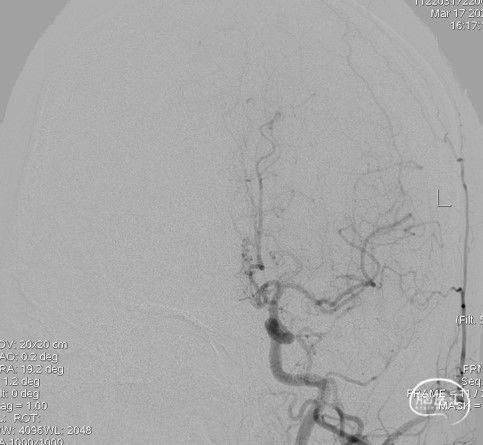

造影:右侧颈内动脉末端变细,大脑前及大脑中自起始部闭塞,脑底少量烟雾血管形成,汇聚使R-MCA少量分支显影。

右侧颈内动脉正位: